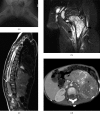

Neuroblastoma is one of the most common malignant neoplasms in childhood. The most common clinical presentation of this tumour is abdominal mass. However, affected children may have various clinical presentations as a result of disseminated metastatic disease or associated paraneoplastic syndromes at the time of diagnosis. In this article we have outlined the imaging findings in seven patients with "extra-abdominal" presentation of neuroblastoma and the pitfalls in making the correct diagnosis. The purpose of this pictorial review is to alert the general radiologist to the possible presentations of this common childhood malignancy to derive early detection and diagnosis.